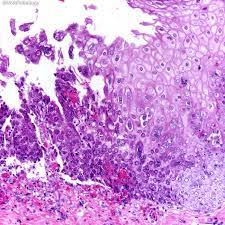

Hsv Esophagitis Pathology / Pathology Of The Esophagus - Peptic strictures cause a gradually progressive dysphagia for solid foods.. Common forms of esophagitis include reflux esophagitis, infectious esophagitis, pill esophagitis candida esophagitis (see the image below) is the most common type of infectious esophagitis. Cytomegalovirus esophagitis is a form of esophagitis associated with cytomegalovirus. The latter can occur frequently during anesthesia or deep sedation. Herpes esophagitis is a viral infection of the esophagus caused by herpes simplex virus (hsv). The esophagus is a tube composed of a mucosal lining, and longitudinal and circular smooth muscle fibers.

Cytomegalovirus esophagitis is a form of esophagitis associated with cytomegalovirus. Herpes esophagitis is a viral infection of the esophagus caused by herpes simplex virus (hsv). Herpes esophagitis is a viral infection of the esophagus caused by herpes simplex virus (hsv). Symptoms include dysphagia, upper abdominal pain, diarrhea, nausea, vomiting, and sometimes hematemesis. Very few cases of a multiple viral infection have been reported. Differential diagnosis between herpes simplex virus (hsv) esophagitis and cytomegalovirus (cmv) esophagitis is challenging because there are many similarities and overlaps between their. Common forms of esophagitis include reflux esophagitis, infectious esophagitis, pill esophagitis candida esophagitis (see the image below) is the most common type of infectious esophagitis. Swallowed food and liquids normally pass through it. Eosinophilic esophagitis attributed to gastroesophageal re. Infective esophagitis is a rare disease, affecting mostly immunocompromised patients. Healing and relapse of severe peptic esophagitis after treatment with omeprazole. Esophagitis can occur from irritation from toxic or abrasive materials ingested or from gastric reflux. The esophagus is a tube composed of a mucosal lining, and longitudinal and circular smooth muscle fibers.

February 3 2020 Week 2 School Of Medicine Pathology Uab from www.uab.edu This condition occurs in the setting of patients with a weakened immune system who are susceptible. Symptoms include dysphagia, upper abdominal pain, diarrhea, nausea, vomiting, and sometimes hematemesis. Occurs with patients who have oral lesions reflux esophagitis 1. Esophagitis can cause painful, difficult swallowing and chest pain. Infective esophagitis is a rare disease, affecting mostly immunocompromised patients. Esophagitis may cause odynophagia and even esophageal hemorrhage, which is usually occult but can be massive. The esophagus is a tube composed of a mucosal lining, and longitudinal and circular smooth muscle fibers. Very few cases of a multiple viral infection have been reported.

Swallowed food and liquids normally pass through it. Esophagitis can cause painful, difficult swallowing and chest pain. Causes of esophagitis include stomach acids backing up into the esophagus, infection, oral medications and allergies. Common forms of esophagitis include reflux esophagitis, infectious esophagitis, pill esophagitis candida esophagitis (see the image below) is the most common type of infectious esophagitis. Symptoms include dysphagia, upper abdominal pain, diarrhea, nausea, vomiting, and sometimes hematemesis. Very few cases of a multiple viral infection have been reported. We present a case of combined cytomegalovirus. It connects the pharynx to the stomach; As the practice shows, hypodiagnostics of eosinophilic esophagitis and other eosinophilic gastrointestinal diseases takes place. Cytomegalovirus esophagitis is a form of esophagitis associated with cytomegalovirus. Esophagitis, also spelled oesophagitis, is a disease characterized by inflammation of the esophagus. Herpes esophagitis is a viral infection of the esophagus caused by herpes simplex virus (hsv). Infective esophagitis is a rare disease, affecting mostly immunocompromised patients.

Occurs with patients who have oral lesions reflux esophagitis 1 hsv esophagitis. Swallowed food and liquids normally pass through it.